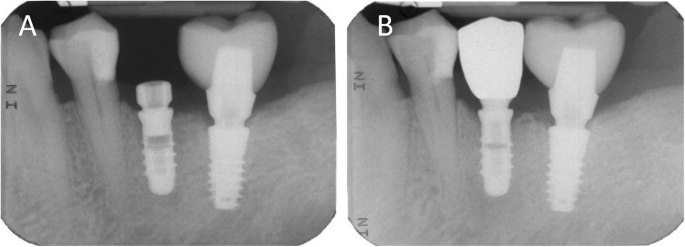

Clinical application of the MZC (Fig. 7). The patient was called back to the dental clinic, and the temporary PMMA crown was removed and replaced with the definitive MZC. At the time of application, the dentist carefully checked the congruity of the shape and volumes of the tooth, the quality of the interproximal contact points and the occlusal contacts, and the quality of the marginal fit and closure. Control of the marginal fit and closure of the restoration took place both clinically and radiographically. Before cementation with temporary cement (Tempbond®, Kerr, Orange, CA, USA), the MZC was positioned and an endoral x-ray was taken. Clinical control of the marginal closure occurred under 4.5x magnification (Zeiss 4.5x®, Zeiss, Oberkochen, Germany), with physical probing of the circumference of the crown with a periodontal probe to intercept any misfits, gaps or undercuts. Occlusal control was very careful and performed with occlusion papers so that any light precontacts were polished. At the end of these checks, and once the aesthetic adaptation of the restoration and the colour had been verified, the crown was cemented and the patient was included in a program of annual checks (two professional hygiene sessions a year, with one planned every 6 months).

Radiographic controls before and after the prosthetic restoration. (A) Endoral periapical radiograph taken at the beginning of the restorative process, before the first intraoral scan, with the healing abutment in position. (B) Three years later, the crown is in function and seated with high precision over the abutment, with little or no gap